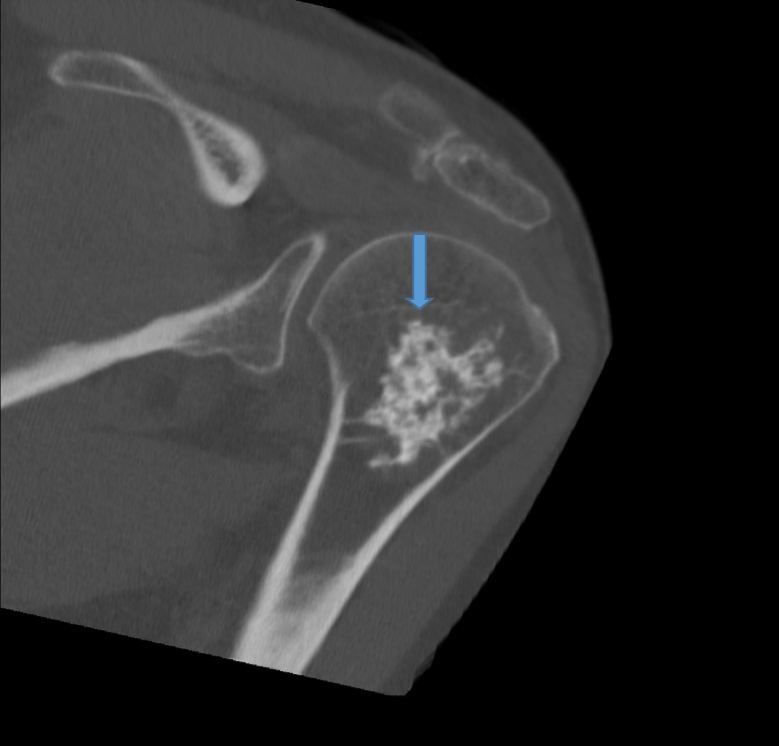

Based on the appearance of the lytic lesion in this patient, the orthopedic physician’s clinical judgement was that it was benign. Consequently, he repeated the radiographs (Figure 2). Even though the chance of malignancy (low-grade chondrosarcoma) is approximately 1%, this patient had noncontrast CT (Figure 3) and MRI (Figure 4) scans.

Figure 3. Noncontrast axial computed tomography (CT) of the left shoulder reveals a lobulated lesion within the proximal humeral metaphysis with chondroid matrix, consistent with enchondroma. The adjacent cortical bone is intact. The lesion measures approximately 5 cm in length.